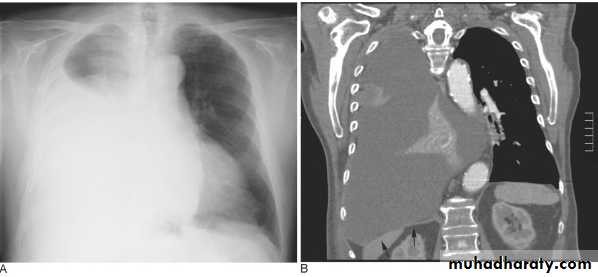

Massive pleural effusion with mediastinal shift to the left.

(A) Chest radiograph(B) CT coronal reconstruction. A massive effusion displaces the mediastinum to the left. CT shows the important pleural effusion together with the enhanced atelectatic left lung.

Note also the depression of the right hemidiaphragm (arrows).